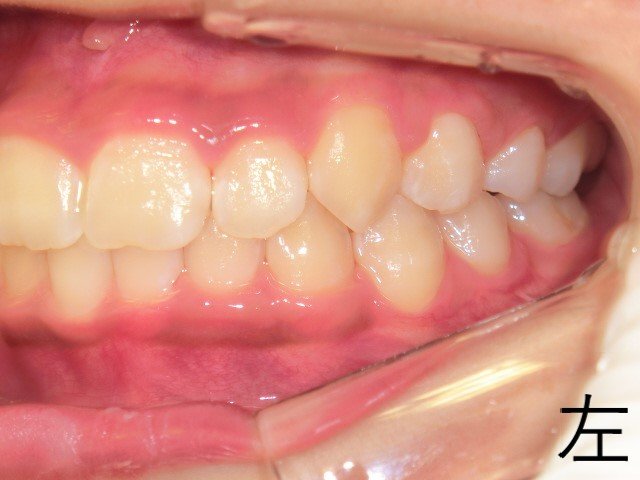

【治療終了時の咬合状態】

12歳時点で、右左ともに上下臼歯の噛み合わせが安定し、良好な咬合が確認されました。

・ 11歳6か月時:上顎の拡大が進んでいたものの、左上乳犬歯が残存しており、犬歯の萌出スペースが不足

・ 12歳時:上顎の拡大がさらに進行し、左上犬歯が正常な位置に萌出し、歯列に収まりました